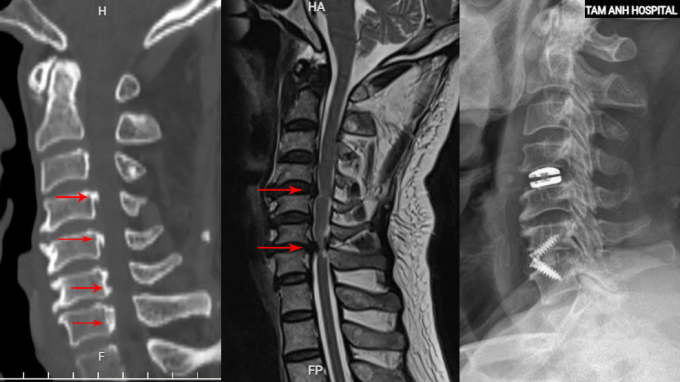

Chụp cắt lớp vi tính CT tại Bệnh viện Đa khoa Tâm Anh Hà Nội phát hiện bệnh nhân vôi hóa nhiều đoạn dây chằng dọc sau. ThS.BS Tạ Ngọc Hà, khoa Chấn thương Chỉnh hình, giải thích lớp dây chằng này có nhiệm vụ giữ vững cột sống, bị canxi hóa và dày lên, làm hẹp ống sống từ đốt sống cổ C3 đến C7. Chụp cộng hưởng từ MRI cho thấy đĩa đệm C4-5 thoát vị, C6-7 thoát vị nặng, chèn ép tủy cổ nghiêm trọng.

Tổn thương vôi hóa dây chằng dọc sau (trái), thoát vị đĩa đệm (giữa) của bệnh nhân được khắc phục sau phẫu thuật (phải). Ảnh: Bệnh viện Đa khoa Tâm Anh